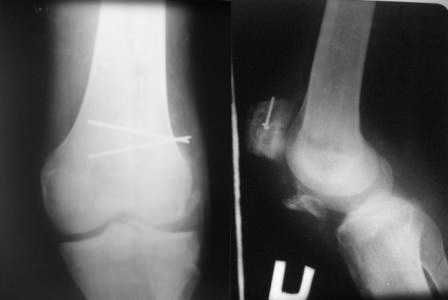

Обратился б-ной С. 1986г.р с застарелыми переломами надколенника и таранной кости, сросшийся переломом обеих локтевых отростков. 25.07.07.г. упал с 6-го этажа. Оперирован в г. Тюмени в гор. б-це 15.08.07.г.:Судя по рентген снимкам остеосинтез обеих локтевых отростков по Веберу, остеосинтез правого надколенника (каким способом не понял ), фиксация гипсовой повязкой правой н/к, гипс снят через 40 дней (со слов б-го.) Обратился в начале декабря, с жалобами на отсутствия активного разгибания в пр. коленном суставе, боли и отечность в обл. пр. г/стоп. сустава и стопы. Больной ходит самостоятельно с палочкой, сильно хромает на правую ногу, гипотрофия квадрицепса, активное разгибание abs, в обл. г/стопного сустава умеренная отечность, актив. и пассив. движения почти в полном объеме, слегка болезненная, при осевой нагрузке боль усиливается, Сделана Р-графия локтевых суставов, пр. коленного и г/стопного суставов. Спицы и проволоки из локтевых отростков удалены. Я больному обещал, что выйду на форум, посоветуемся и вместе решим, что делать. 1. Из -за ретракции м/тканей репозиция отломков надколенника не удается, что делать? 2. Перелом таранной кости- вроде схватка имеется но с кистозными изменениями, может не трогать? Заранее благодарю !!

прилагаю снимки надколенника.

Имеем дело с застарелым повреждением разгибательного аппарата и контрактурой коленного сустава. Согласен с д.Джолдасом - лечить как повреждение собственной связки надколенника. Учитывая сроки после травмы, возможно не получиться сопоставить костные фрагменты. Я бы рекомендовал сделать аутопластику собственной связки надколенника ( способ Лазишвили с соавт.)с блокированием проволочной петлей. Способ очень эффективен при многооскольчатых переломах надколенника,либо аллотендопластику собственной связки ( в ваших условиях можно использовать лавсановую ленту).После восстановления собственной связки возможно придется переместить головки квадрицепса либо произвести некоторые элементы миофасциотенотомии (Решается на операционном столе)

То, что надо оперировать надколенник - всем понятно, вопрос - как?

могу предложить 2 варианта ( теоретически, своего опыта нет)

1 если опытный хирург, готовый на большую операцию, норимальное физиотерапевтическое отделение и умный больной - мобилизация квадрицепса и одномоментная репозиция и фиксация надколенника

в противном случае - небольшой аппарат Илизарова на голень, спицу на полукольце через надколенник и дозированно низводить надколенник. когда низведете - погружной остеосинтез.

И последнее. дистальный отдел надколенника небольшой, наверняка будет крайне остеопоротичный, так что стабильно надколенник Вы не синтезируете. Поэтому надо обязательно при синтезе првести проволочную петлю над верхним полюсом надколенника и через бугристость большеберцовой кости 0 разгрузить место синтеза. Впрочем, это банальность и Вы наверняка без меня знаете

В приложении фото пациента с переломом надколенника 3 месячной давности. После мобилизации отломков, 4 главой мышцы бедра и полного разгибания голени оставался диастаз между костными фрагментами в 2 см. В связи с этим наложили модуль из аппарата Илизарова - 2 опоры и 2 спицы (в верхнем полюсе надколенника и верхней трети большеберцовой кости). Очень медленно (в течение 15 минут) путем накручивания гаек на стержнях растянули 4 главую мышцу бедра и устранили диастаз. Аппарат демонтировали и выполнили остеосинтез <стягивающей петлей>. Через 6 месяцев фиксаторы удалены. Автор данного <хирургического трюка> профессор из Австрии Vilmos Vecsei (<Гений ортопедии>, 2004, № 4, С. 94-95). Ваш случай не совсем идентичный по давности травмы и малой величине дистального отломка, но описанный <трюк> может оказаться полезным и при выполнении операции, которую рекомендует Джолдас.